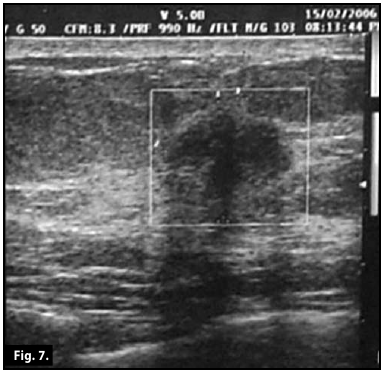

Ultrasound scan...